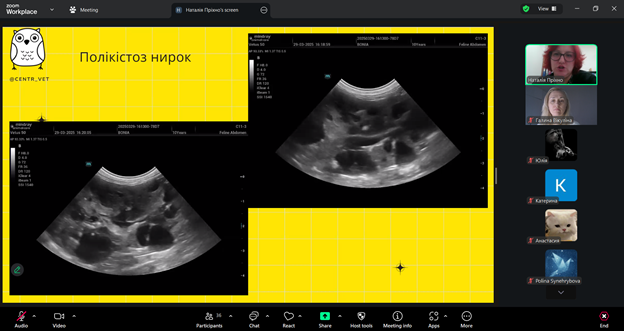

Лектор – Наталія ПРІХНО, яка є кардіологом, лікарем з УЗД даної ветеринарної клініки, розповіла про те, як правильно працювати з УЗД-апаратом, на що звертати увагу під час обстеження котів і собак та які «підводні камені» можуть чекати під час інтерпретації зображень. Було багато корисних порад і реальних випадків з практики — саме те, що найбільше цінують слухачі. Пані Наталія детально пояснила принципи проведення AFAST/TFAST, ключові орієнтири обстеження та їхнє значення у клінічній практиці. Учасники мали змогу ознайомитися з типовими патологіями, які можуть бути виявлені за допомогою цих протоколів, а також з поширеними діагностичними помилками та способами їх уникнення. Окрему увагу було приділено практичним клінічним випадкам, що продемонстрували ефективність AFAST/TFAST у швидкій оцінці стану тварини, прийнятті рішень у невідкладних ситуаціях та моніторингу динаміки стану пацієнта.